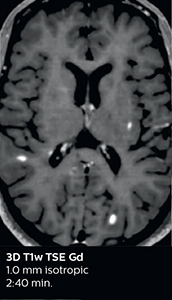

Using MultiBand SENSE allowed the staff to improve their diffusion quality. “Our diffusion sequence was already fast before, about 40 seconds. Now with Elition, it still lasts 40 seconds, but we improved the spatial resolution by 0.2 mm and use high b-values to be more sensitive to visualize changes related to acute stroke,” says Dr. Savatovsky. “We now also developed a high resolution DTI sequence (1.3 x 1.3 x 2 mm) that can be reformatted and takes 2 to 5 minutes depending on the coverage. We use it every time we have a doubt, or when we expect the diffusion to be abnormal but don’t see that on the fast sequence. We occasionally spot small ischemic infarctions that would not have been visible with the regular diffusion sequence.”

This is an example of acute ischemic stroke with distal occlusion of the right posterior cerebral artery. Note the improved visibility of the ischemic territory on the diffusion weighted image with high b-value. The 3D FLAIR shows a distal PCA occlusion. The fast SWIp depicts the thrombus on the isolated second echo image. The total scan time (including SmartBrain, preparations and a fast 3D T1w TSE Gd) is 8:00 minutes.